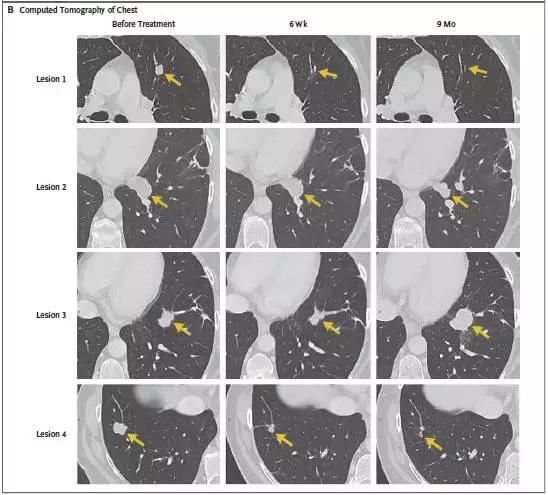

转移性结直肠癌患者肿瘤患者经过TIL细胞疗法治疗后,7个肺部的转移灶在几周后都变小乃至消失!

晚期胆管癌肝转移的患者,术后出现双肺多发转移,经过TIL细胞疗法治疗后已经被临床无进展生存了!